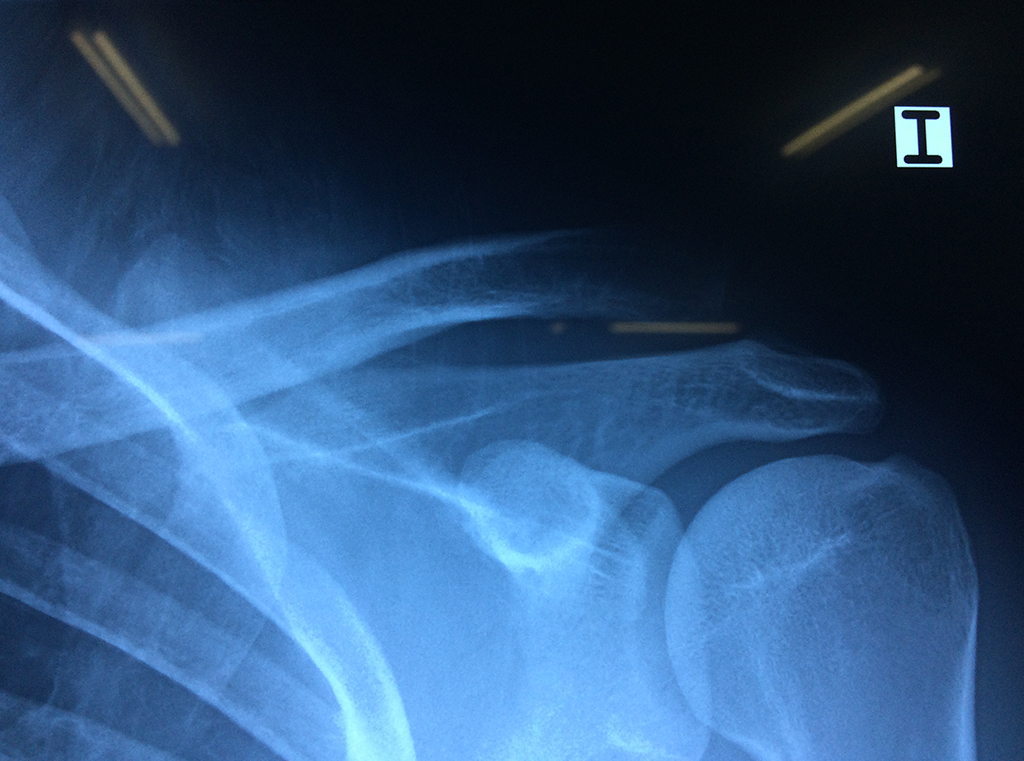

Varias estructuras transparentes en forma de saco llamadas bolsas serosas, permiten el deslizamiento suave de los diferentes componentes móviles. El hombro es la articulación con mayor amplitud de movimientos del cuerpo humano.